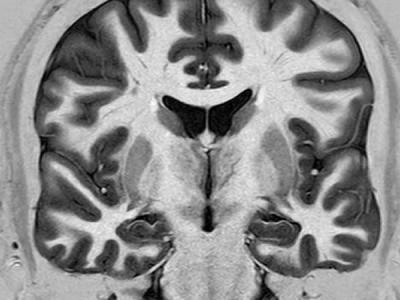

英国科学家研发出新的测谎技术 “测谎技术”在各个领域的应用一直都非常广泛,但...